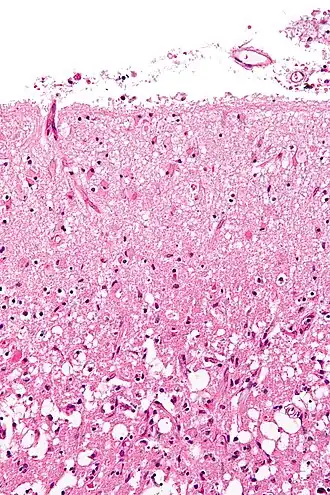

A astrogliose (também conhecida como astrocitose ou astrocitose reativa) é um aumento anormal no número de astrócitos devido à destruição dos neurônios próximas a um trauma no sistema nervoso central (SNC), infecção, isquemia cerebral, um acidente vascular cerebral (AVC), uma resposta autoimune e uma doença neurodegenerativa. No tecido neural saudável, astrócitos desempenham um papel crítico no fornecimento de energia para os neurônios, regular o fluxo sanguíneo, a homeostase do fluido extracelular assim como dos íons e transmissores, e regular a função sináptica e a remodelação sináptica.[1][2] A astrogliose altera a expressão molecular e a morfologia dos astrócitos, provocando a formação de cicatrizes e, em casos graves, a inibição da regeneração de axônios.[3][4]

A astrogliose é um conjunto de alterações no astrócitos que ocorrem em resposta a todas as formas de dano e doença do SNC. As alterações produzidas pela astrogliose reativa variam com a gravidade do dano do SNC através de uma série de alterações progressivas na expressão molecular, hipertrofia celular progressiva, proliferação e cicatrização.[3]